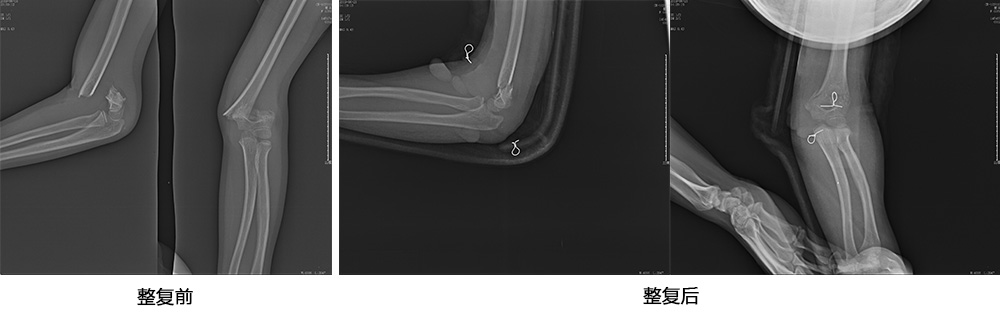

傳統(tǒng)手法整復(fù)病例影像

CR103119